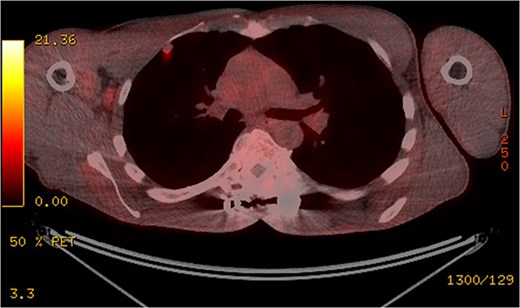

Subsequent computed tomography (CT) scan and positron emission tomography (PET) scan (Figs 2 and 3) confirmed the presence of three nodules in the right lung, suspicious for sarcoma metastases. An anterior, pleural-based upper lobe lesion, a posterior lower lobe lesion, and a lesion located at the bifurcation of his right middle and lower lobes.

The pleural-based anterior right lobe lesion showed fluorodeoxyglucose uptake on a PET scan.